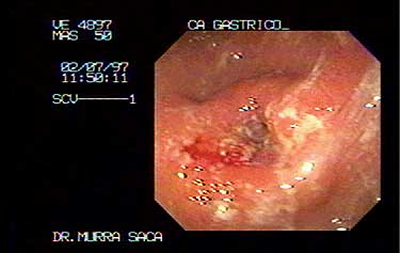

Paciente Masculino de 50 años:

Con carcinoma obstructivo del antro Gástrico.